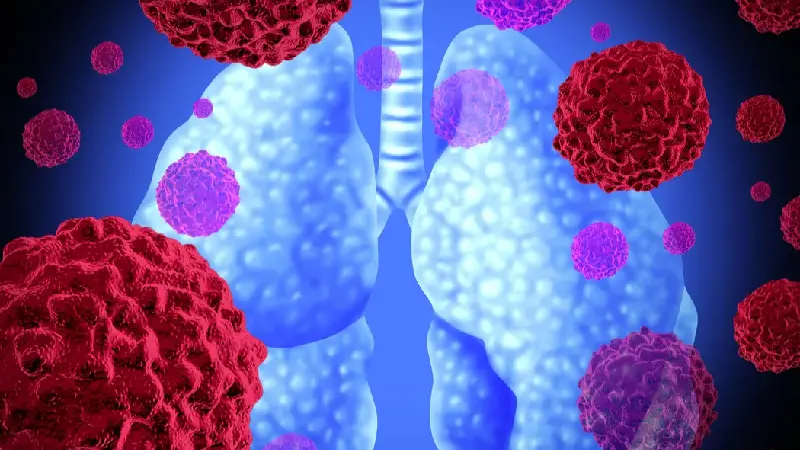

شکل 1. نمونهای از تومور موجود در ریه که توسط پیکانی بر روی رادیوگرافی قفسه سینه نشان داده شدهاست.

سرطان ریه معمولاً در مجاری هوایی (برونش یا برونشیول) یا کیسههای هوایی کوچک (آلوئول) ریههای شما شروع میشود. سپس میتواند به سایر اندامها گسترش یابد.